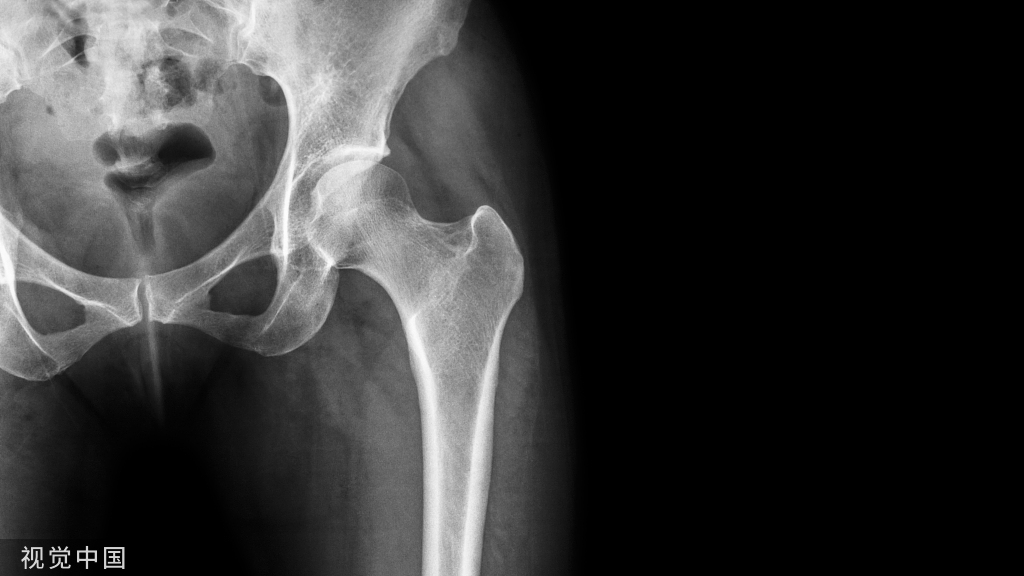

桡骨远端骨折属于常见的上肢骨折疾病,随着社会发展,工作及生活节奏不断加快,车祸和高处坠落等也会使得桡骨远端严重骨折的发生率明显上升。

桡骨远端骨折属于上肢较为常见的骨折疾病,在实施评估的时候,通常进行计算机断层扫描(CT)分类,且在所有分类系统中应用x射线的时候,观察者之间的一致性程度显示为中等到中等。